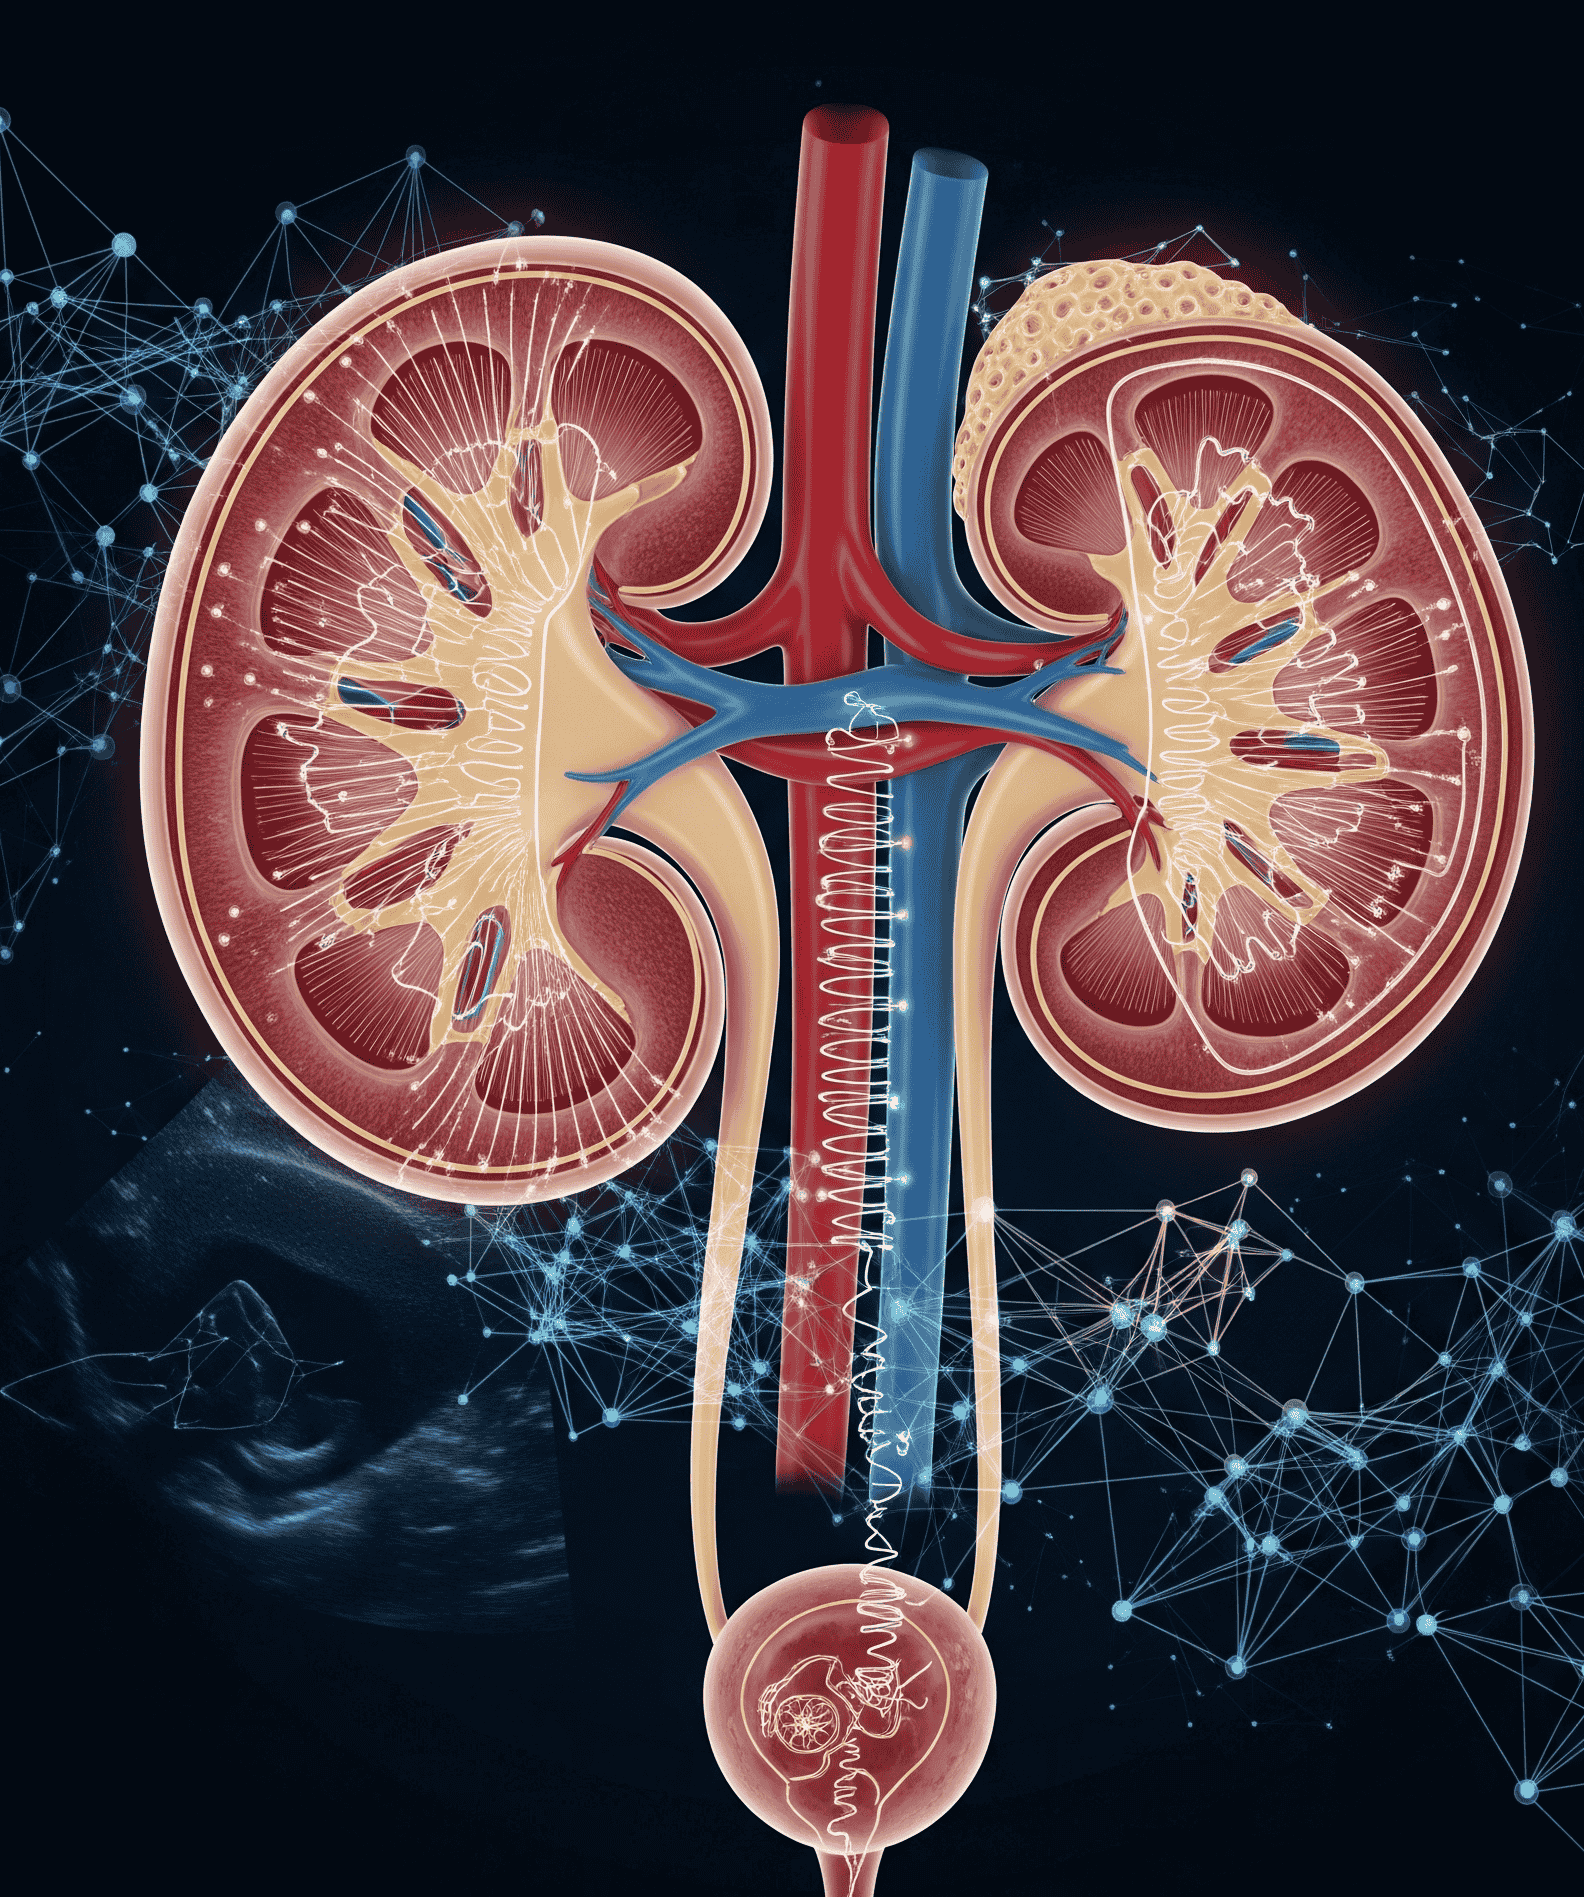

Journal of Nephro-Urologic Pathways

Journal of Nephro-Urologic Pathways is a focused, peer-reviewed journal committed to driving forward both foundational research and clinical advancements in nephrology and urology. It highlights the intricate biological, molecular, and physiological...